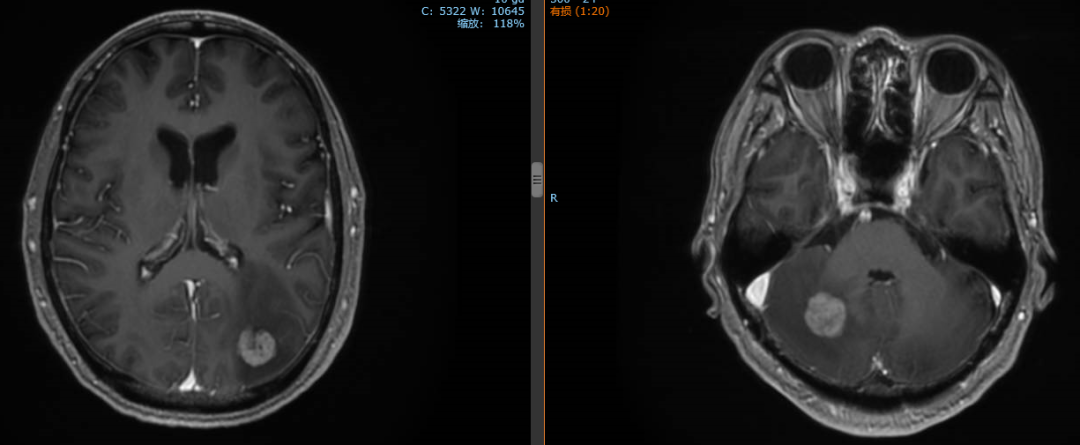

2020年1月患者出现头痛症状,复查脑MR示:枕叶及右侧小脑半球多发结节,结合病史考虑转移灶。

经影像学评估后,患者肝脏、双肺、颈部淋巴结无进展。

2020年1月13日开始对左侧枕叶及右侧小脑转移灶进行放疗,PTV-GTV=44.5Gy/9F